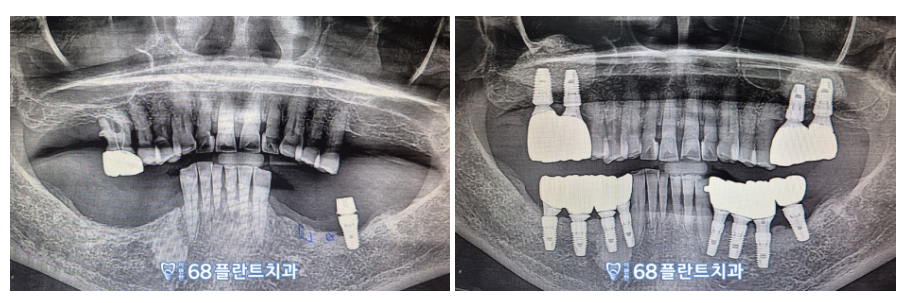

◆ 전 > 후 ◆

(2024.02.26ㅡ>2024.09.17)

환.자분께서 한동안 앞니를 활용하여

식사하고 계시어

많이 불편해 하셨는데,

철산역치과 이편한68플란트치과에서

치료 후 편안하게 식사를 하고 계신다며,

매우 흡족해하셨답니다!